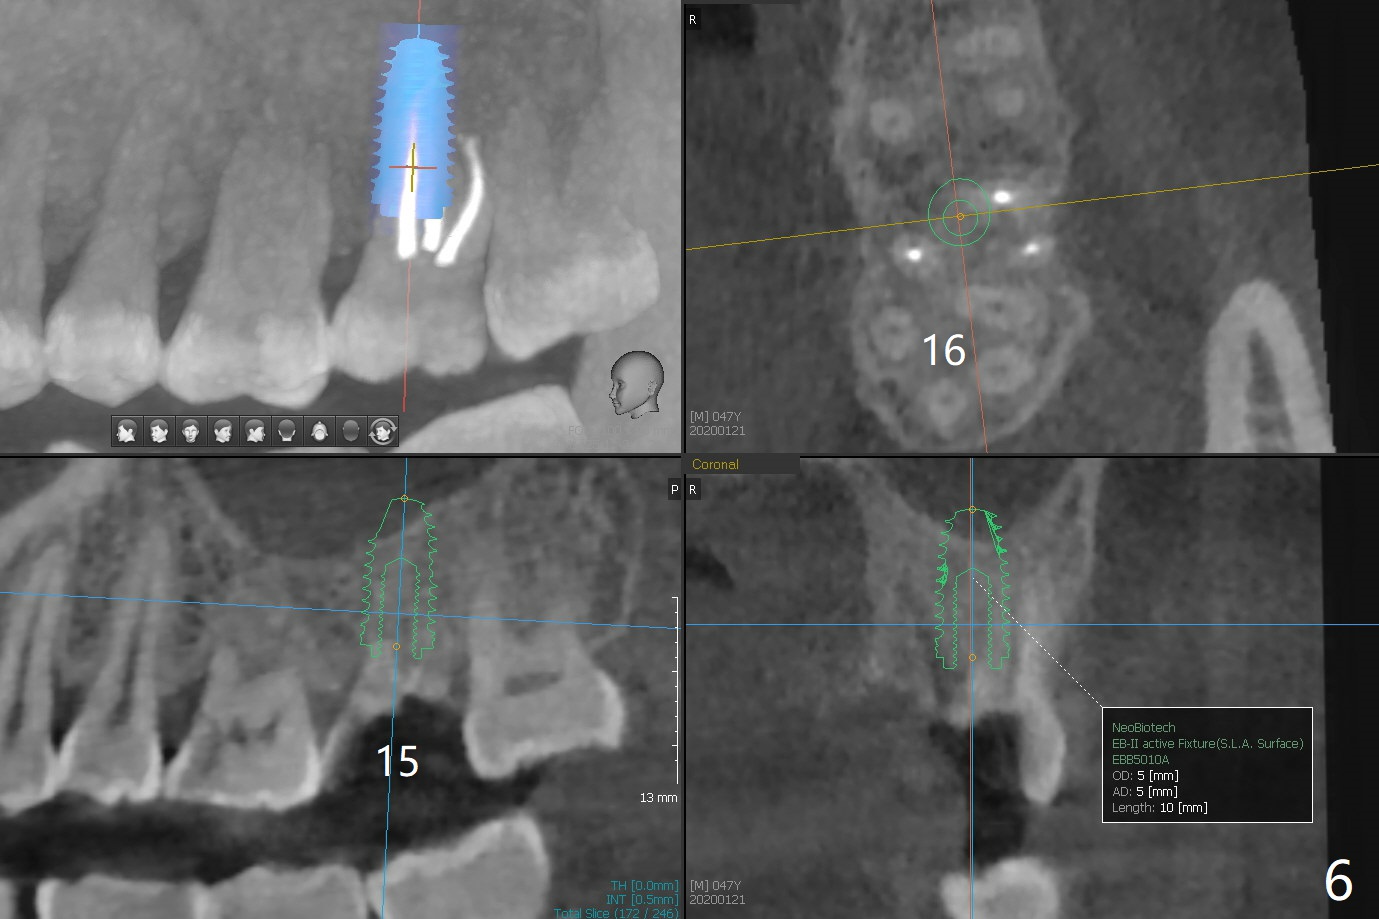

A 47-year-old man has pain at #2 and 15, while #14 has mesiolingual subgingival fracture (Fig.1). #2 is deemed non-salvageable by an endodontist, whereas RCT is finished at #15. When the patient returns for restoration, he reports that the filling is out at #15. In fact it has subcrestal fracture (Fig.2), while #14 equicrestal and difficult to restore (Fig.3). Although the patient agrees to have implants at #2 and 15, DB bone loss at #2 makes it difficult for implant (Fig.4). Use FC implant for primary stability. Insert a small piece of cotton pellet or healing screw and pack sticky bone around the implant before placing a temporary abutment. The latter will form a large gingival cuff, which makes it easy to place pair abutment without interference from the crestal bone. Screw loosening will be reduced. In fact there is PARL of the palatal root of #14 (Fig.5). A FC implant will be also placed at #15 for the same reason (Fig.6).